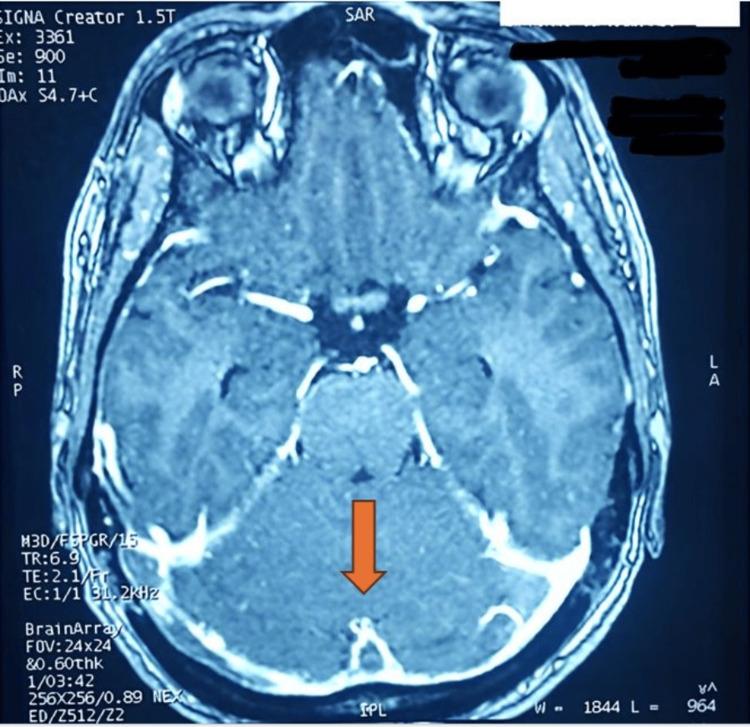

Rapid ascent to altitudes above 8,000 feet (2,500 meters) is known to be associated with acute mountain sickness (AMS), but its role as a cause of cerebrovascular disorders is rarely described. Cerebral venous sinus thrombosis is a rare and potentially fatal condition that can frequently be misdiagnosed. In this article, we report an unusual case of a 27-year-old woman who developed an extensive cerebral venous sinus thrombosis (CVST) during an expedition in the Atlas Mountains. The underlying mechanisms explaining this event will be discussed in light of this clinical observation.

众所周知,快速攀升至海拔8000英尺(2500米)以上会引发急性高原病(AMS),但其作为脑血管疾病病因的作用却鲜有描述。脑静脉窦血栓形成是一种罕见且可能致命的病症,常常容易被误诊。在本文中,我们报告了一例不同寻常的病例,一名27岁女性在阿特拉斯山脉探险期间发生了广泛的脑静脉窦血栓形成(CVST)。我们将根据这一临床观察结果讨论解释该事件的潜在机制。